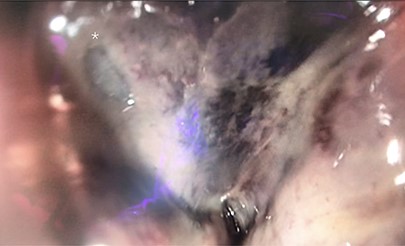

In retrospect, the patient reported anal pain during administration of a fleet enema 3 days prior. On inspection of the anus, there was a necrotic area leading into the anal canal. This finding of perianal trauma associated with the increasing evidence of sepsis led to a presumptive diagnosis of FG. CT scan (Fig. 2) demonstrated an area of hazing and small amounts of free gas within the perirectal tissue suggestive of a rectal perforation or FG. The patient was taken to theatre for an urgent intervention. The scrotum and perianal region required debridement of the affected soft tissue (Fig. 1). Sigmoidoscopy demonstrated circumferential necrosis of the lower portion of the rectum consistent with REI (Fig. 3). A decision was made to expectantly manage the rectal injury and perform a repeat sigmoidoscopy with the aim of preserving the rectum in lieu of an urgent rectal resection. The antibiotic regime was changed to meropenem, clindamycin and vancomycin. Tissue cultures from the debridement grew scant colonies of Pseudomonas aeruginosa and Bacteroides uniformis. The repeat sigmoidoscopy demonstrated stabilization of the rectal ischaemia. A diverting colostomy was created to assist in application and management of negative pressure dressings to the perineal wound (Fig. 4). He required 2 days of post-operative ICU support and over the next 2 weeks, symptoms and inflammatory markers returned to normal. An examination under anaesthesia performed 1 week later demonstrated interval improvement of the rectal mucosa with resolving necrosis. The patient was discharged after 3 weeks with no further dressings and the colostomy was reversed 3 months later.

Sigmoidoscopic still of site of rectal injury. Site of perforation marked with Asterix*.